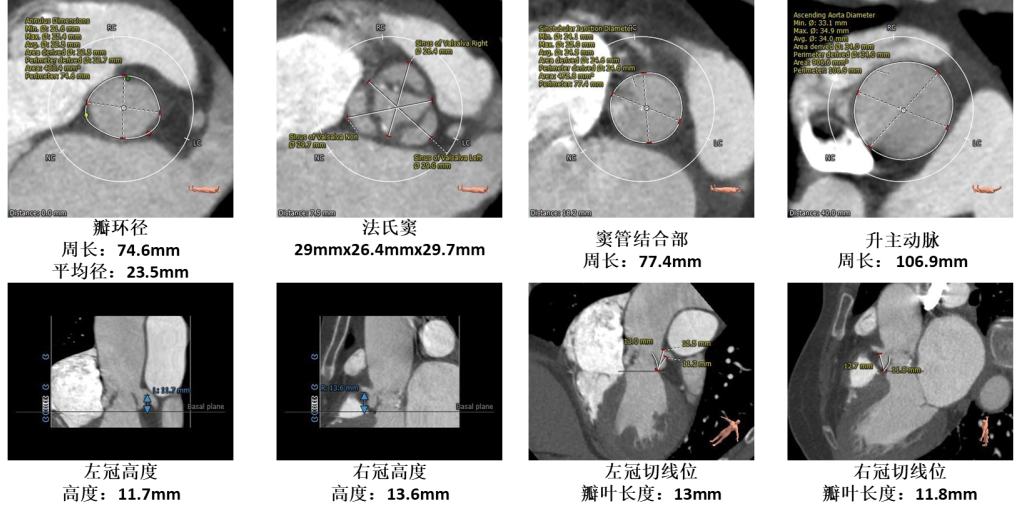

术前评估

1.主动脉瓣瓣环周长74.6mm,平均径23.5mm。

2.三叶式主动脉瓣,瓣叶增厚,瓣叶边缘少量零星钙化,未见明显粘连。

3.左右冠开口高度尚可,瓣叶冗长,左冠瓣叶长度>瓣叶附着缘到冠脉开口距离。

4.瓦式窦内径、窦管交界、升主动脉内径可 。

5.非横位心,主动脉弓距及弓部、夹角可。

6.双侧股髂动脉无明显钙化迂曲,整体入路直径良好。

主动脉根部评估